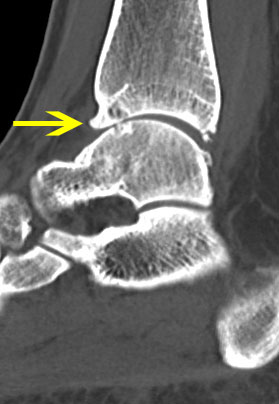

Abbildung 13-14, Video 7

Osteochondrale Läsion an der rechten medialen Talusschulter. Die Knorpelfläche erscheint bei der initialen Inspektion häufig intakt, erweist sich dann bei der Tasthakenpalpation allerdings als deutlich weicher verglichen mit dem umliegenden intakten Knorpelgewebe. In den meisten Fällen lässt sich mit dem Tasthaken ein Riss in der Oberfläche nachweisen und eine lose chondrale bzw. osteochondrale Schuppe abheben. Die instabilen Knorpelanteile und die sklerotisch veränderten Anteile der subchondralen Knochenschicht müssen mit einer Kürette oder einem Shaver entfernt werden, bis ein stabiler Rand aus gesundem Knorpelgewebe besteht. Die Eröffnung des subchondralen Knochens erfolgt mit einer gebogenen Ahle. Anschließend (ggf. nach dem Öffnen der Blutsperre) sollten kleine Blutungen aus den Knochenkanälen erkennbar sein.